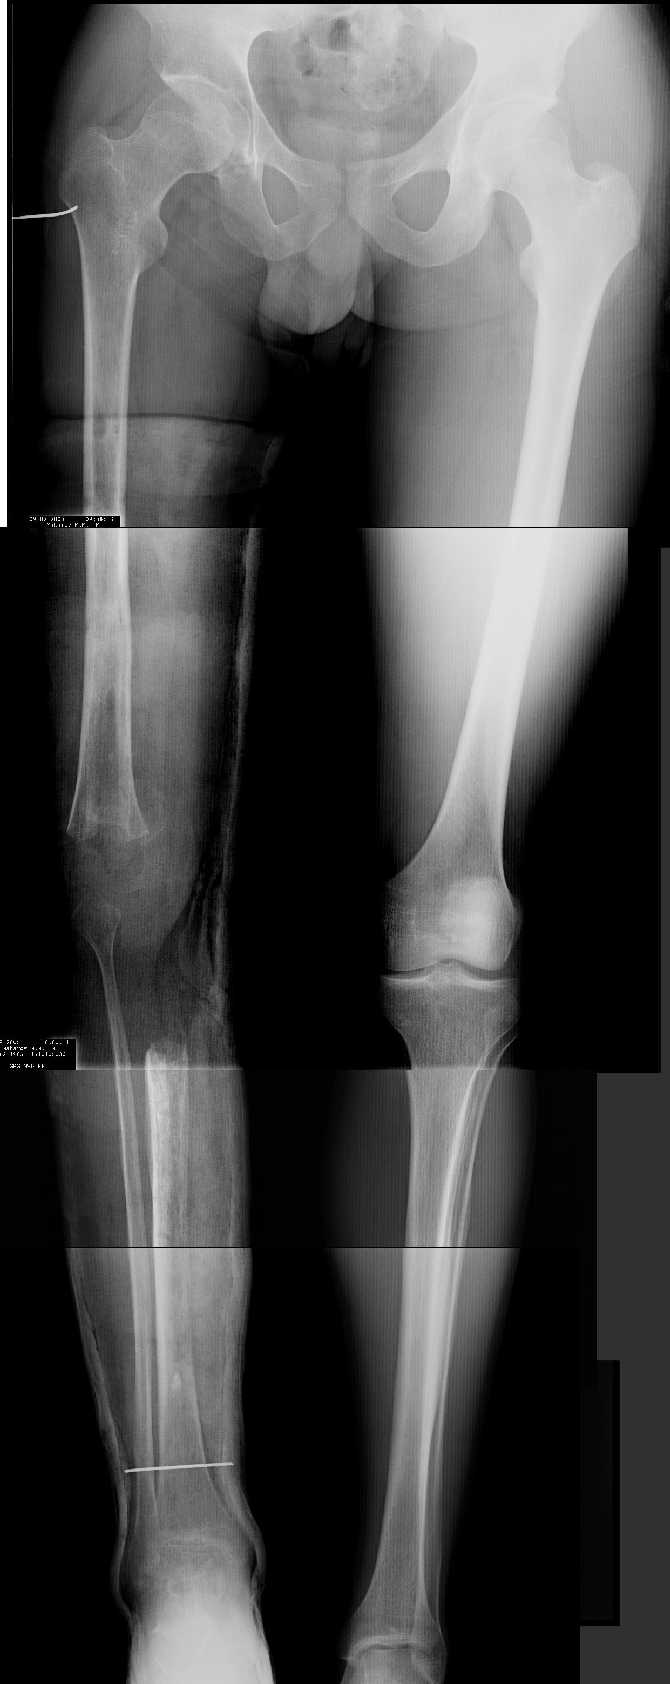

Женщина, 29 лет.В 2001 году получила политравму (таз, открытый многооскольчатый перелом правой бедренной кости на границе средней и нижней трети со смещением,

открытый перелом правой голени, пятки, закрытый - правого надколенника, поперечного отростка L4, пальцев кисти, сотрясение головного мозга).

Переломы конечностей лечились АВФ.В настоящее время стойкая разгибательная контрактура правого коленного сустава (сгибание 105-110 гр., разгибание 160-165 гр.), варусная деформация, болевой синдром.

Даже по этим коротким снимкам видно, что варусная деформация на уровне бедра. Хотя для полноценной оценки оси сделать надо снимок всей конечности, от таза до стопы. Наклеить метки на кожу, по которым сделать склейку. И профиль бы тоже неплохо посмотреть.

Уважаемый Антон, при определении уровня остеотомии и величины коррекции руководствуемся, обычно, необходимостью обеспечить нормаль механической оси к середине опорной поверхности большеберцовой кости. Расчет производится по рентгенограмме (рентгенограммам) конечности под нагрузкой, которые визуализируют положение головки бедренной кости относительно таранной кости. На представленных рентгенограммах определить эти реперные точки (и заслужить Вашу зараннюю благодарность) не представляется возможным. Остается неясным с каким исходом сросся перелом правой большеберцовой кости. Складывается впечатление, что нанесены не механические, а анатомические оси. Исправлять проще за счет "минус - кость", но механически правильнее "плюс". Чтобы выполнить механические требования, иногда на ряду с угловой коррекцией (деваризация-экстензия, т.к. имеется не только разгибательная, но и сгибательная контрактура)необходимо медиолатеральное смещение.

имеется S-образная деформация бедра на фоне "многооскольчатого

перелома правой бедреннойљ кости на границе средней и нижней трети со смещением"

Уважаемый Антон, видимо перелом большеберцовой кости на механическую ось не повлиял, но явно варусная деформация усугубляется повреждением наружного связочного аппарата (МКС.... Просится поднагрузочный R-снимок конечности и корригировать, на мой взгляд, надо бедро (+ остеотомия, если планируется мобилизация коленного сустава).